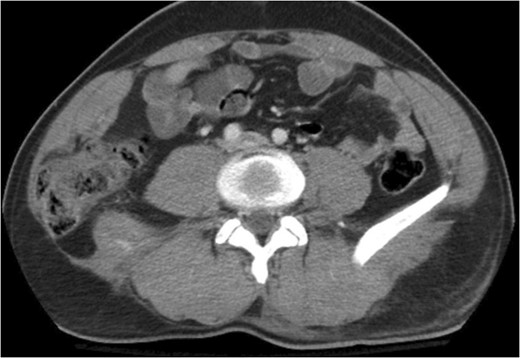

A 43-year-old male patient presented with a right-sided traumatic lumbar hernia after a blunt mechanism. The patient had been pinned between a dirt-mover’s claw arm resulting in a crush mechanism. He sustained injuries to the lumbar spine, sacrum, abdominal wall and 12th rib. On presentation, he did not have clinical or radiographic evidence necessitating abdominal exploration and was observed in a monitored setting. Computed tomography imaging demonstrated a Grynfeltt defect with herniation of the ascending colon and cecum through an area defined by the 12th rib, quadratus lumborum and internal oblique (Figures 1 and 2). After several days of observation and recuperation, the patient continued to have significant pain overlying the hernia site. We electively brought him to the operating room on post-injury Day 4. A laparoscopic repair of the traumatic hernia was performed. Key operative steps included: (i) Wide exposure of the hernia defect via incision of the peritoneum and transversalis as well as mobilization of the ascending colon and duodenal sweep (Figures 3 and 4). (ii) Primary repair of the defect with intra-corporeal suturing of the oblique musculature (Figures 5 and 6). (iii) Placement of an underlay mesh with appropriate redundancy at least 4 cm in all directions around the defect and seating against the iliac crest (Figure 7). Post-operative imaging demonstrates obliteration of the hernia defect and restoration of the abdominal wall (Figures 8 and 9). The patient has recovered, returned to the work force and has no pain or bulge at the repair site 6 months after injury.

The traumatic lumbar hernia is seen on the right side of the abdominal wall above the iliac crest on computed tomography.